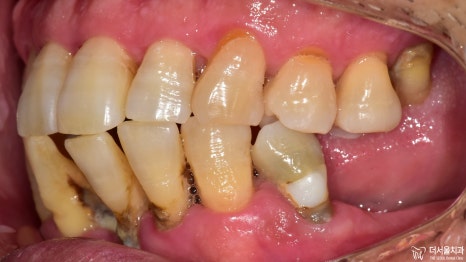

2) 측면

이쪽도 정면과 마찬가지였습니다.

구강 내에 전체적으로 번진 치주 질환 때문에

잇몸 및 치아의 상태가 좋지 않습니다.

처음 검진을 했을 때 보다

더 심각한 구강상태를 갖고 있었습니다.

아무래도 2년이 넘는 시간 동안

아무런 치료를 받지 않으셨기 때문에

더욱 악화된 것 같네요.

보시다시피 하악 전치부의 문제들이 심각했습니다.